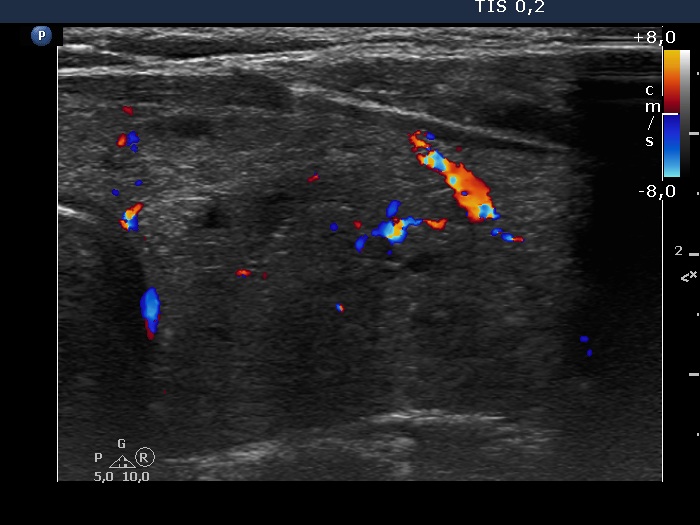

Consecutive patients with the final diagnosis of Hashimoto's thyroiditis - case 21 (1268) (ultrasonographic picture 11)

Left lobe, transverse scan, color Doppler mode. The vascularization is not typical.